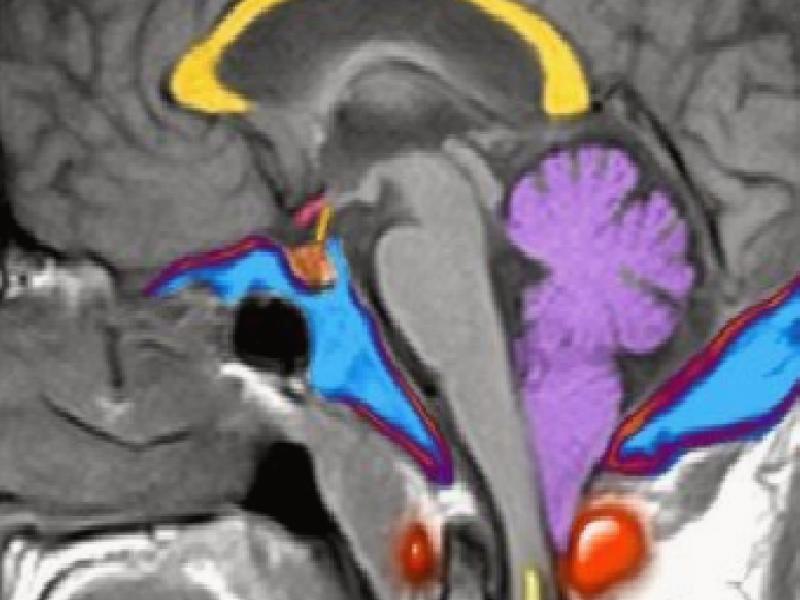

It is also called primary cerebellar ectopia. The cerebellar tonsils herniated into the upper cervical spinal canal more than 3 mm from the level of the foramen magnum. This downward slide occludes the CSF circulation between the spinal cord and the intracranial nerve. In this way, it can cause fluid accumulation in the spinal cord called syringomyelia or hydromyelia.

Magnetic Resonance Imaging (MRI): It is important for obtaining a full anatomical image and has no side effects because it uses a magnetic field. By imaging the brain, cerebellum, brain stem and spinal cord, information can be obtained about the diagnosis of Chiari I malformation and the presence of accompanying additional anomaly.